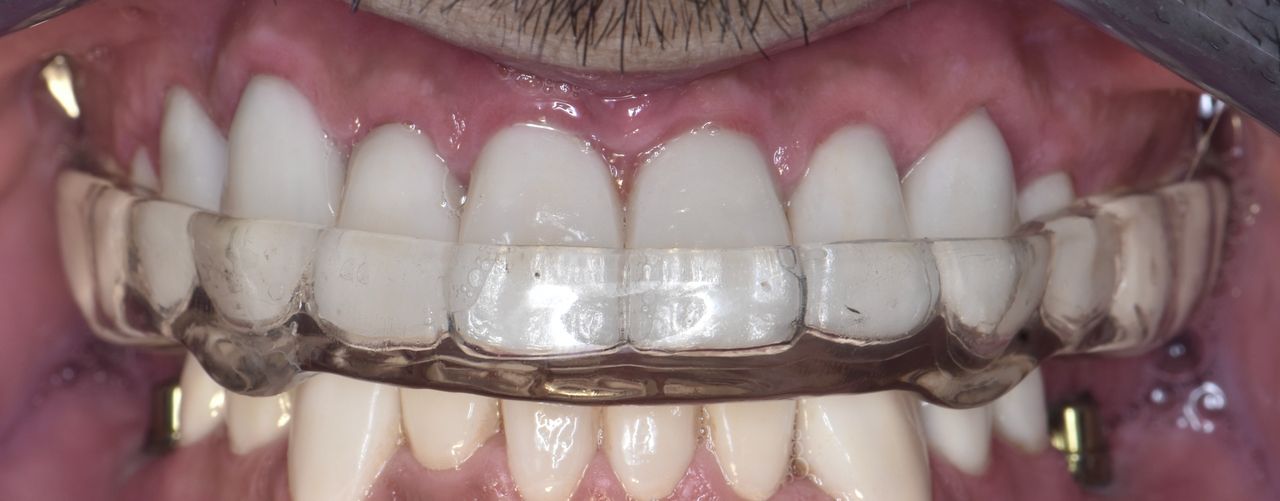

Los implantes dentales son la forma mas estética y funcional de sustituir una diente perdido, ya sea por caries, enfermedad periodontal, traumatismo o agenesia. Lo mas importante para que este tratamiento sea exitoso es su correcta planeación.